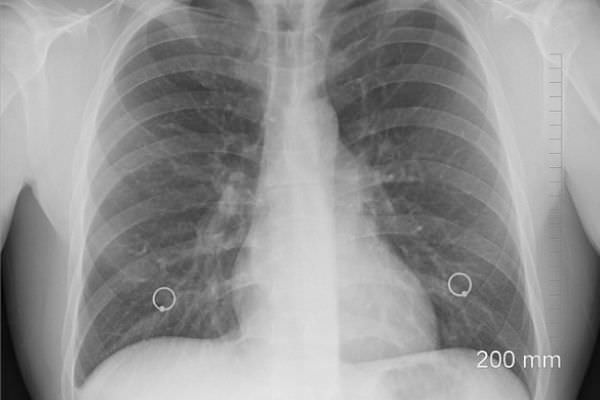

Флюорография – это диагностическая процедура, целью которой являются скрининговые исследования органов грудной клетки для раннего выявления различных патологий и заболеваний в органах грудной клетки. Многие курильщики интересуются, можно ли курить после флюорографии? Учитывая, что процедура проводится безболезненно и быстро на специальном оборудовании и не предусматривает инвазивного вмешательства, запрета на курение до и после флюорографии не существует. Тем не менее, надо поговорить о том, какие результаты никотиновой зависимости может показать флюорография, и стоит ли губить свое здоровье, выкуривая ежедневно не одну сигарету.

Сегодня прохождение флюорографии 1 раз в год всеми гражданами страны является обязательной процедурой, которая позволяет на самых ранних стадиях диагностировать такие патологии, как туберкулез, рак легких и др. Особенно это важно для курильщиков с большим стажем уничтожения собственного организма.

Благодаря этому методу диагностики удается своевременно выявлять нарушения, требующие немедленного лечения и спасения жизней больных. Флюорография помогла многим людям не только избавиться от тяжелых недугов, но и побороть никотиновую зависимость. Известны случаи, когда только одного взгляда на снимок собственных легких, пораженных многолетним потреблением никотина, хватало человеку для того, чтобы навсегда отказаться от сомнительного удовольствия.

Уникальность флюорографии заключается в том, что независимо от того, курили ли вы перед исследованием, на снимке будет видно все до мельчайших деталей.